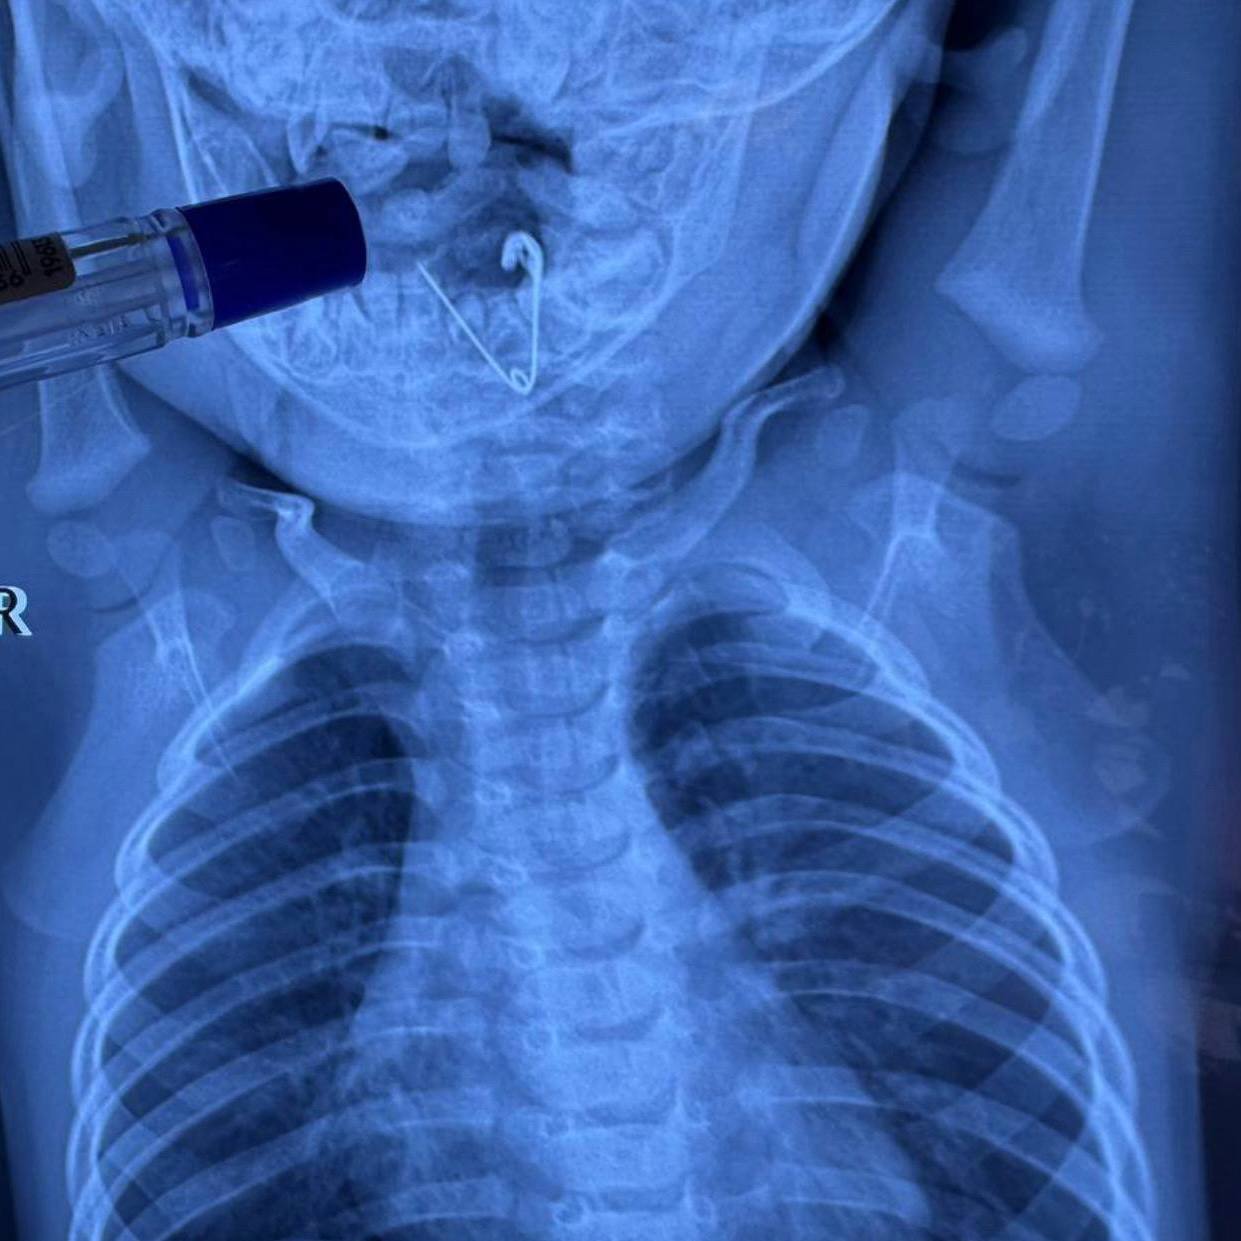

Семимесячный малыш из Черниговского района чуть не погиб, проглотив открытую булавку. Родители заподозрили неладное, когда у ребёнка внезапно начались сильный кашель и слюнотечение. Булавка, оставленная мамой как оберег, оказалась во рту малыша.

После рентгена его экстренно госпитализировали в краевую детскую больницу Владивостока. Врачи с помощью эндоскопа аккуратно извлекли предмет. Сейчас малыш уже улыбается, а мама может вздохнуть с облегчением.